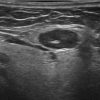

Hạch tuyến nước bọt

» Thông tin: Nữ giới – 66 tuổi.

» Lâm sàng: Sưng đau vùng góc hàm.

# Hạch lành tính ngoại vi tuyến nước bọt dưới hàm.